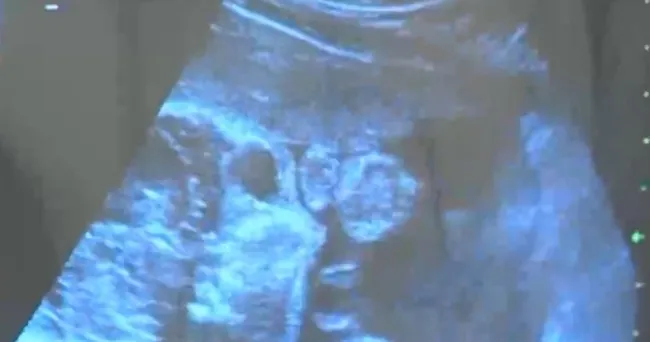

İngiltere’de yapılan bir araştırma, tüm dünyayı heyecanlandırdı. 346 hamile kadının sağlık verilerini inceleyen bilim insanları, erken doğumun önüne geçebilecek bir bakteri türü tespit etti.

İngiltere'de 346 hamile kadının sağlık verilerini inceleyen bilim insanları, erken doğumun önüne geçebilecek bir bakteri türü tespit etti.